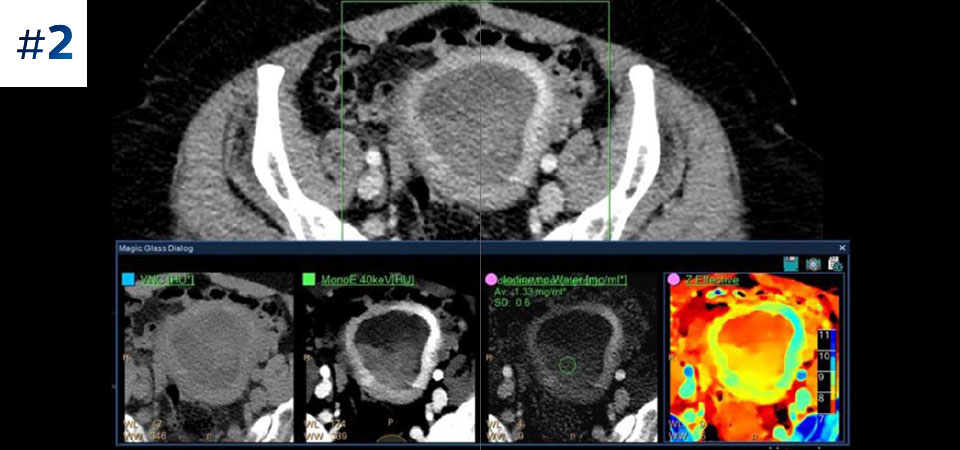

Umflătură la nivelul gâtului

Prin tomografia computerizată bazată pe detector spectral, puteți achiziționa date la mai multe nivele de energie - convenționale și spectrale – printr-o singură expunere și fără protocoale speciale de scanare, pentru o mai bună caracterizare și vizualizare a țesuturilor.

Scanează ca de obicei O singură scanare pentru date convenţionale şi spectrale obţinute rapid, cu doză redusă, pentru fiecare pacient, de fiecare dată.

Are întotdeauna disponibilă componenta spectrală Rezultate 100% spectrale, pentru toate scanările care sunt întotdeauna disponibile la cerere, chiar și retrospectiv.